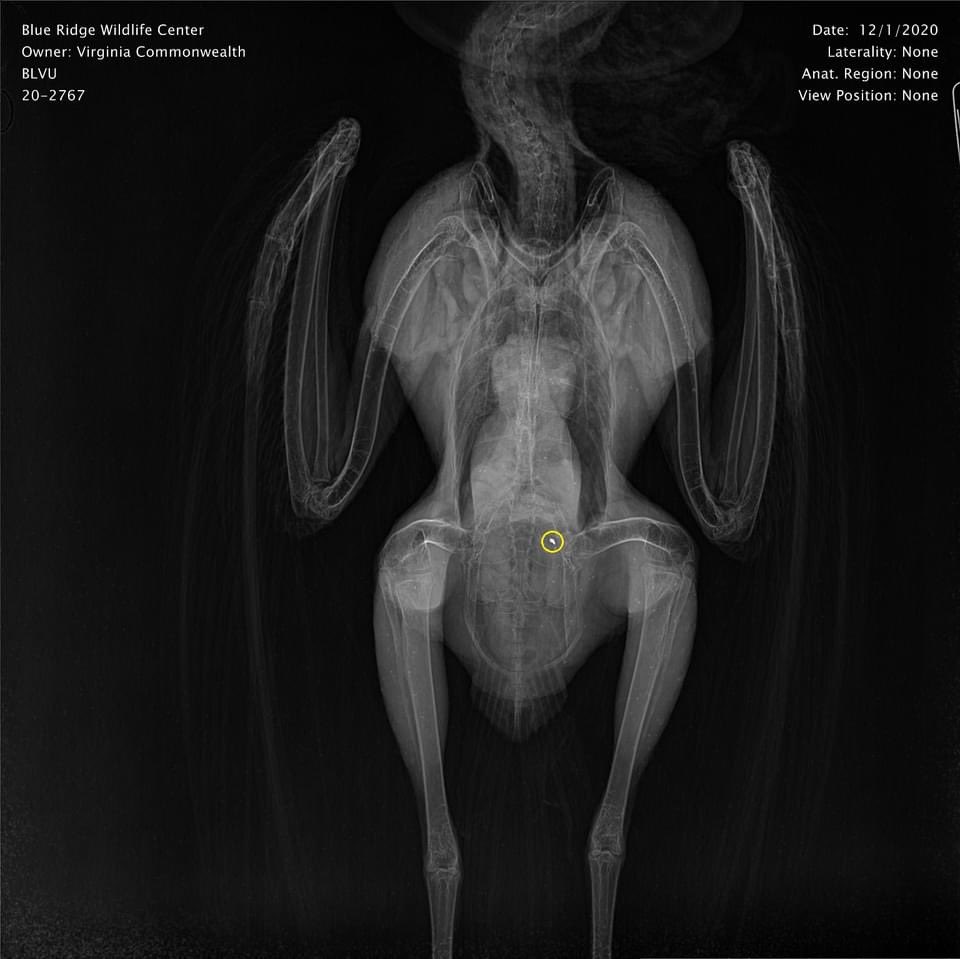

On 12/1, we received TWO lead poisoned vultures that came in just hours apart – one Black Vulture and one Turkey Vulture. Both still had lead fragments in the gastrointestinal tract and were suffering from severe signs of the poisoning.

Unfortunately, the Turkey Vulture passed away the following morning despite intensive treatment. The Black Vulture is looking better today, but this patient’s prognosis is still guarded.